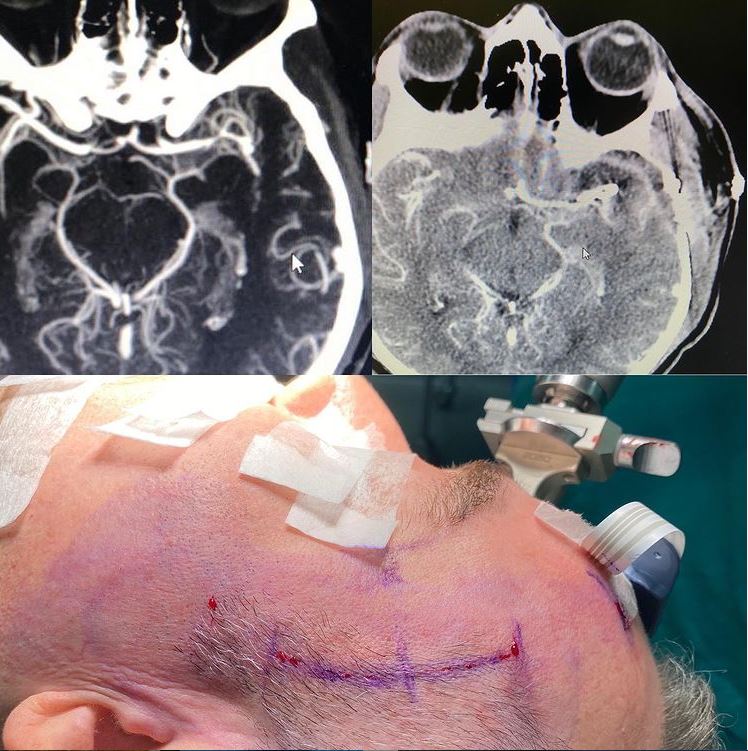

Clipaje de Aneurisma